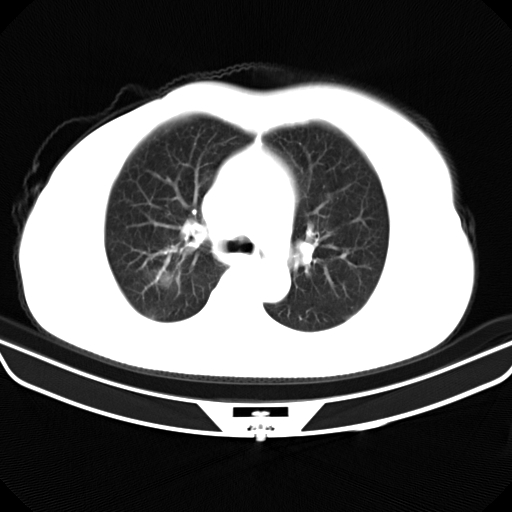

以下是引用zjzjr在2007-3-23 13:28:00的发言:[br]右肺上叶后段可见一结节状高密度影,可见毛刺征,胸膜凹陷征及血管导入征,纵隔内可见肿大淋巴结影.考虑右肺上叶周围型肺癌伴纵隔淋巴结转移.

以下是引用zjzjr在2007-3-23 13:28:00的发言:[br]右肺上叶后段可见一结节状高密度影,可见毛刺征,胸膜凹陷征及血管导入征,气管前腔静脉后可见肿大淋巴结影.考虑右肺上叶周围型肺癌伴纵隔淋巴结转移.